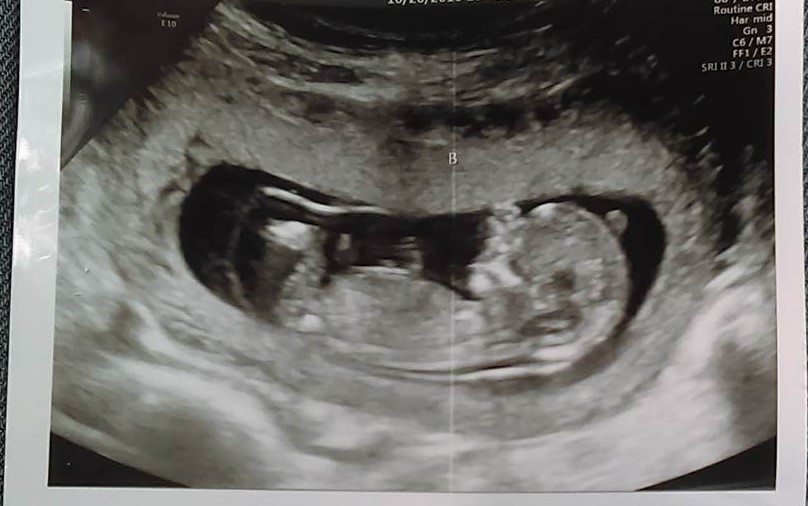

I had a private ultrasound down to find out the gender of my twins. the tech said they were measuring at 12 weeks 4 days so it was still early but she said baby a looks definitely like a girl and baby b she is unsure of but made an educated guess.....what do yall think?